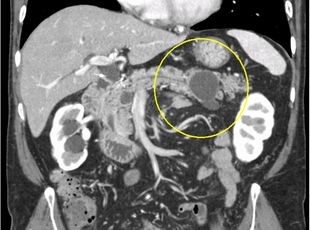

膵体部粘液性嚢胞腫瘍症例